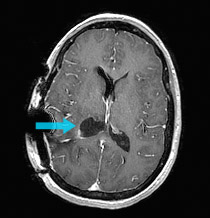

Primary brain tumors among adults are astrocytoma, meningioma, and oligodendroglioma. Only when the man was stable in recovery did. Brain tumors are masses of abnormal cells within the brain. Tumors can grow from the brain tissue itself (primary), or cancer from elsewhere in the body can spread to the brain (metastasis).